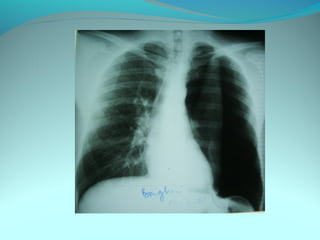

Opacité latéro_trachiale et hilaire droite grossierement arrondie de

6cm de diam dense et homogene

 la limite interne se confend avec le mediastin et la limite externe

nette convexe vers le mediastin

elle confond avec le mediastin évoquant une image mediastinale

Par ailleur on note:

Une surrélevation de la coupole diaph

Un coblement …..

DIAGNOSTIC:

Lymphome H ou NH

Volumineuse ADP tuberculeuse ou sarcoidosique